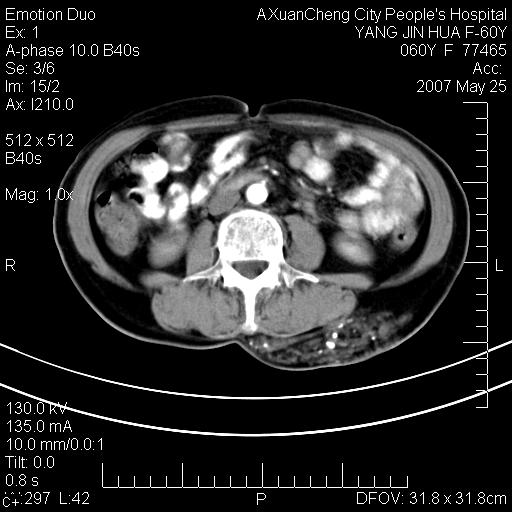

发现左侧腰背部包块40余年,逐渐长大,质软,局部表面可见扩张的血管影

左背部皮下良性肿瘤,密度不均,边界不清,内有脂肪、钙化,增强扫描无明显强化,血管平滑肌脂肪瘤?进一步诊断有困难,建议穿刺活检。

左侧背部皮下混杂密度肿块,结构较疏松,边缘欠光整,内有多发斑点状钙化,考虑:皮下血管瘤。

其内可见斑点状静脉石,血管瘤有时就不增强化,还是血管瘤。

1、病灶内有小点状钙化,静脉石?这可是血管瘤诊断的重要征象

2、病灶内有脂肪组织增生,血管瘤有此特点

还是考虑皮下血管瘤,强化不明显可能跟大量血栓形成有关,好多战友考虑血管平滑肌脂肪瘤,血管平滑肌脂肪瘤的血管就不强化么?只要有血管就都应该强化。